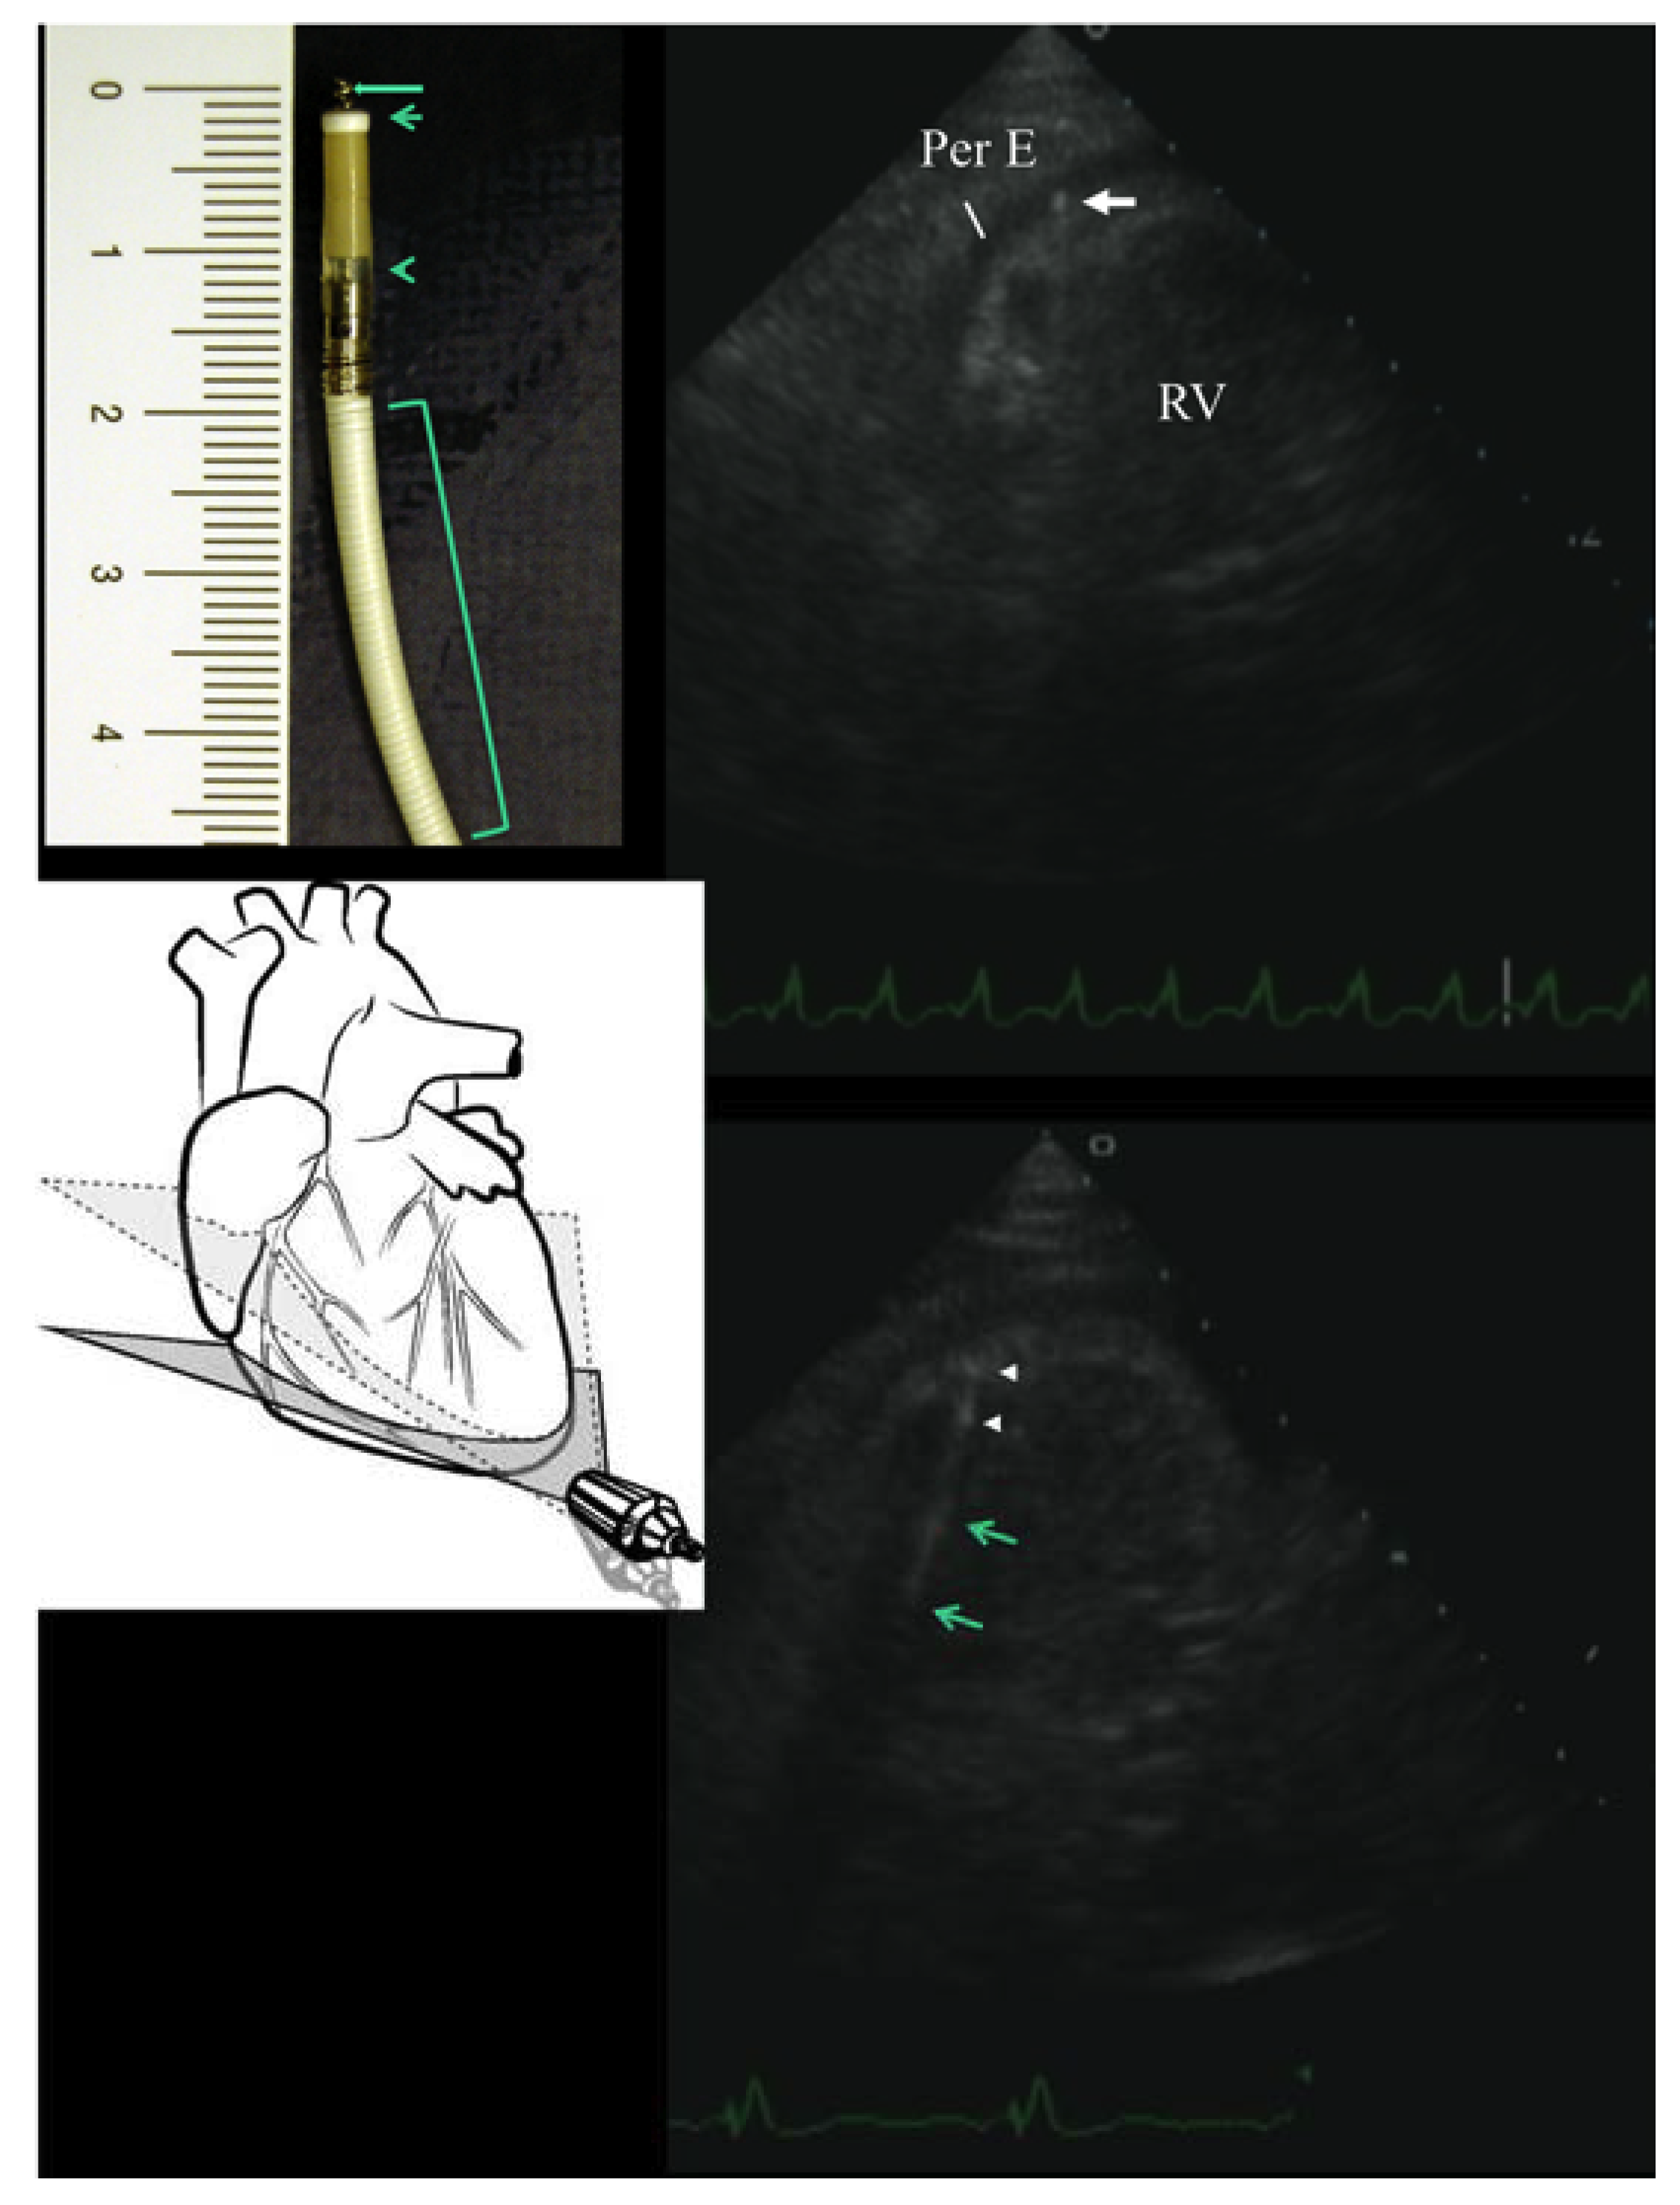

The patient was thus scheduled for urgent pericardiocentesis; before the procedure, a new echocardiographic examination, specifically aimed at best visualizing the tip of the catheters, was performed (Figure 2). A four-chamber view with a sub-apical approach, in order to transect the true apex, allowed a full visualization of the ventricular lead to the apex (Figure 2) and by a slight downward inclination of the tomographic plane (as schematically shown in the Figure 2), we focused on the tip of the ventricular lead that had unequivocally penetrated into the pericardial space by a few mm. On the basis of knowledge of the Riata lead structure (Figure 2), it was evident that the visualized displaced ‘tip’ was mostly the fixating screw (helix) of the Riata lead (Figure 2).

As the cause of the pericardial effusion with impending tamponade was quite clear, we decided to cancel the pericardiocentesis procedure and first of all remove the cause of the pericardial irritating stimulus and in the meantime, temporarily treat the congestion symptoms with diuretic therapy; this was simply attained by carefully unscrewing the fixating screw (i.e., the extendable/retractable helix for fixation in the ventricle (Figure 2)), along with minimal retraction of the lead, under fluoroscopic monitoring. That procedure was successful and uncomplicated. The same echocardiographic view used for the diagnosis showed the disappearance of the helix from the pericardial space and the visualization of the true tip of the catheter at the right ventricular apex, with no signs of perforation; the tip appeared as a hyperechogenic short area, maximally distally located (the tip electrode), separated by a few mm from another, more proximal, similar hyperechogenic area, that should be related to the ring electrode; also, the distal coil was distinguishable via the long hyper-echogenic area (Figure 2). A successful electrical cardioversion was also performed. In the following days, we observed a clinical and echocardiographic improvement, with complete regression of pericardial effusion on the 20th day (Figure 1). The clinical conditions remained stable, with no relapse of pericardial effusion at the 1-year follow-up.

Echocardiography played a pivotal role in our case. In our view, echocardiography has great potential for handling patients with possible lead complications. This technique has the advantage of being rapidly available at the bedside, a quality which is maximally appreciated in emergencies like our case; it is the principal tool in diagnosing effusion and cardiac tamponade, which are major complications of lead perforation [8]; in addition, it is a non-ionizing radiation method that can afford repeatability without harming the patient, which is pivotal in a clinical situation like ours, where follow-up is crucial. In our case, the prompt recognition of minimal perforation was possible thanks to off-axis tomographic planes (Figure 2). Therefore, a thorough exploration of the catheter course by ultrasound, looking for tip visualization, is important. To orient oneself in lead imaging, very useful internal points of reference are the coil and the electrode, which appear as hyperechoic rings or areas along the catheter course (Figure 2). In our case, the helix, the two rings and eventually, the distal defibrillator electrode were visualized. We found it useful to know a priori the structure of the lead that we were going to explore by echo (Figure 2). The potential of echocardiography in lead imaging is increasing. As recently demonstrated, echocardiography (and in particular intracardiac ultrasound) has the potential to detect the fibrosis encapsulating the lead that brings about complications after infected lead extraction (the formation of new post-extraction masses) [9]. The value of this echocardiographic approach in this setting is also emphasized by the fact that impedance and other electrophysiological parameters didn’t change. A normal impedance doesn’t exclude lead dislocation with minimal cardiac wall perforation [10]. A small perforation, in fact, might result in the cathode being proximal to the epicardium and the anode being proximal to or within the endocardium, resulting in normal pacing parameters [10], as eventually happened in our patient, in whom only the helix clearly reached the pericardial space (Figure 2).

Figure 2. Right ventricular perforation by the ICD lead, visualized by transthoracic echocardiography, before and after lead repositioning. The upper part shows the modified 4-chamber view (the specific inclination of the tomographic plane to attain this plane is schematically shown in the diagram at the bottom left, where the dashed-line-delimited plane indicates the standard 4-chamber view plane orientation), that shows the tip of the wire (due to its minuscule structure, actually the helix) penetrating 2–3 mm into the fluid-filled pericardial space (on the upper left side, a photo of the distal part of the lead is reported, with its characteristics indicated: helix, the fixating screw (long arrow), tip electrode (short arrow), ring electrode (arrow head), and the distal defibrillator electrode (bracket)). The lower part shows the same echocardiographic view after unscrewing the helix, along with minimal lead retraction: no more protrusion of the lead into the pericardial space is visible; in addition, some hypereflective zones along the lead are visible by echo, that should correspond to the electrodes (arrow heads) and coils (arrows). RV = right ventricle; Per E = pericardial effusion.